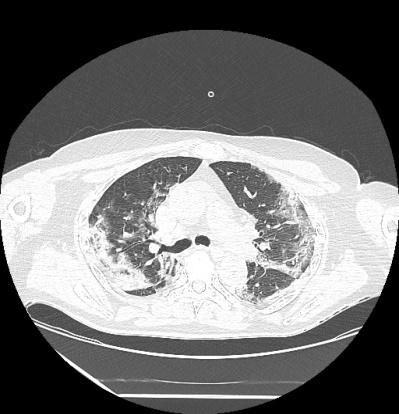

SARS-CoV-2 (Severe Acute Respiratory Syndrome Coronavirus-2) infection appeared for the first time in Wuhan, China in December 2019, and in March 2020 it was declared a pandemic by the World Health Organization (WHO). Thus, a new disease was registered-COVID-19 (Coronavirus Disease 2019). Our study followed the patients who had the diagnosis of obstructive ventilatory dysfunction in their personal pathological antecedents, who tested positive for SARS-CoV-2 infection. The patients were in the hospital records with chronic obstructive pulmonary disease (COPD) or asthma. After discharge, patients had a number of outstanding symptoms: fatigue, cough, dyspnea, mental and cognitive disorders, palpitations, headaches, dysfunctions of taste and smell. All patients underwent pulmonary rehabilitation after hospitalization.

A retrospective study was defined between April 2021-December 2021, including 72 patients who had SARS-CoV-2 infection and who presented various symptoms on discharge. The study was carried out at the Clinical Hospital of Infectious Disease and Pneumoftiziology "Victor Babeș" from Craiova-Pulmonology Department. These patients had a history of obstructive ventilatory dysfunction: asthma or COPD. Patients were monitored during the respiratory rehabilitation program at 3 and 6 months after discharge.

Patients with COPD are increase risk to develop severe forms of COVID-19. Smoking is an important risk factor for SARS-CoV-2 infection and obstructive ventilatory dysfunction. Vaccination against SARS-CoV-2 infection is effective, being associated with mild forms of COVID-19. Pulmonary rehabilitation is a key point in the management of patients with COVID-19, improving exercise capacity, reducing dyspnea, improving health, increasing oxygen saturation and quality of life.